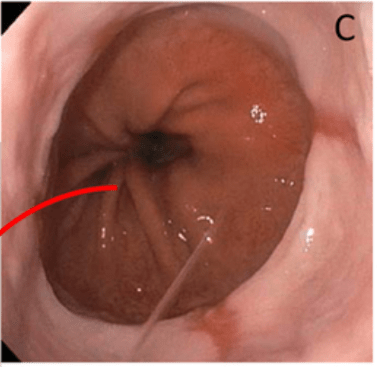

Diagnosis for pathology below (salt and pepper chromatin with 3 mitoses per 2 mm²)

What is atypical carcinoid?

Atypical carcinoids have 2-10 mitoses per 2 mm² or the presence of necrosis.

Typical carcinoids have <2 mitoses per 2mm².